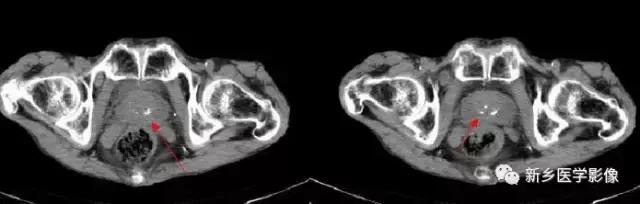

输精管钙化

主要表现为盆腔内对称性小钙化灶。